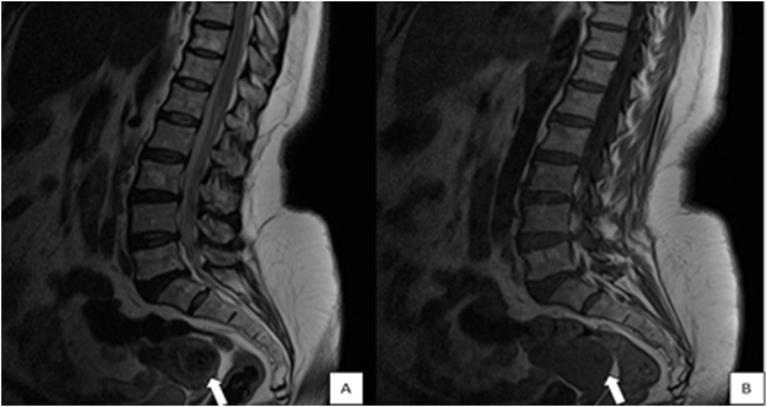

腰椎间盘磁共振成像期间腰椎的偶然椎体外发现。

Incidental extraspinal findings in the lumbar spine during magnetic resonance imaging of intervertebral discs.

To calculate the frequencies of incidental extraspinal findings and incidentally detected congenital anomalies or anatomical differences in the lumbar spine on magnetic resonance imaging (MRI) scans of intervertebral discs.

Of the 379(100%) patients, 90(23.7%) patients were presented with incidental findings. Among the incidental findings, 39(10.3%) were renal cysts, 10(2.6%) were retroverted uteri, 5(1.3%) were Nabothian cysts, 4(1.1%) were ovarian cysts, 10(2.6%) were uterine fibroids, 3(0.8%) were endometrial thickening, 11(2.9%) were indicative of hydronephrosis, 4(1.1%) were uncovered prostatic enlargement, 2(0.5%) were atrophic kidney, and 1(0.3%) each was of an ectopic kidney and bladder wall thickening, respectively.

计算在椎间盘磁共振成像(MRI)扫描中偶然发现的脊柱外异常以及偶然检测到的腰椎先天性异常或解剖差异的发生率。

379例(100%)患者中,90例(23.7%)有偶然发现。在这些偶然发现中,肾囊肿39例(10.3%),子宫后倾10例(2.6%),宫颈纳氏囊肿5例(1.3%),卵巢囊肿4例(1.1%),子宫肌瘤10例(2.6%),子宫内膜增厚3例(0.8%),肾积水11例(2.9%),前列腺增生4例(1.1%),肾萎缩2例(0.5%),异位肾和膀胱壁增厚各1例(0.3%)。